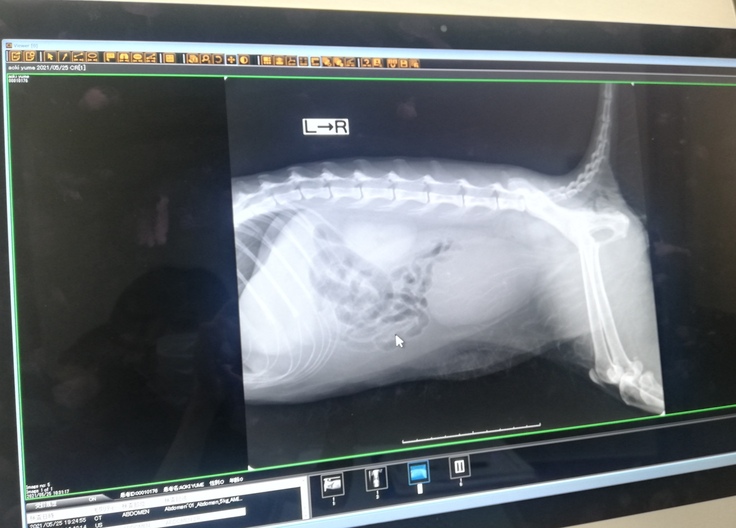

膀胱が大きく膨らんでしまっている様子のレントゲンです。

膀胱がぱんぱんに膨らむまで溜まっていたおしっこを抜いてもらい、少し楽になったのか、なんとか耐えてくれましたが、血液検査結果は非常に悪い数値でした。